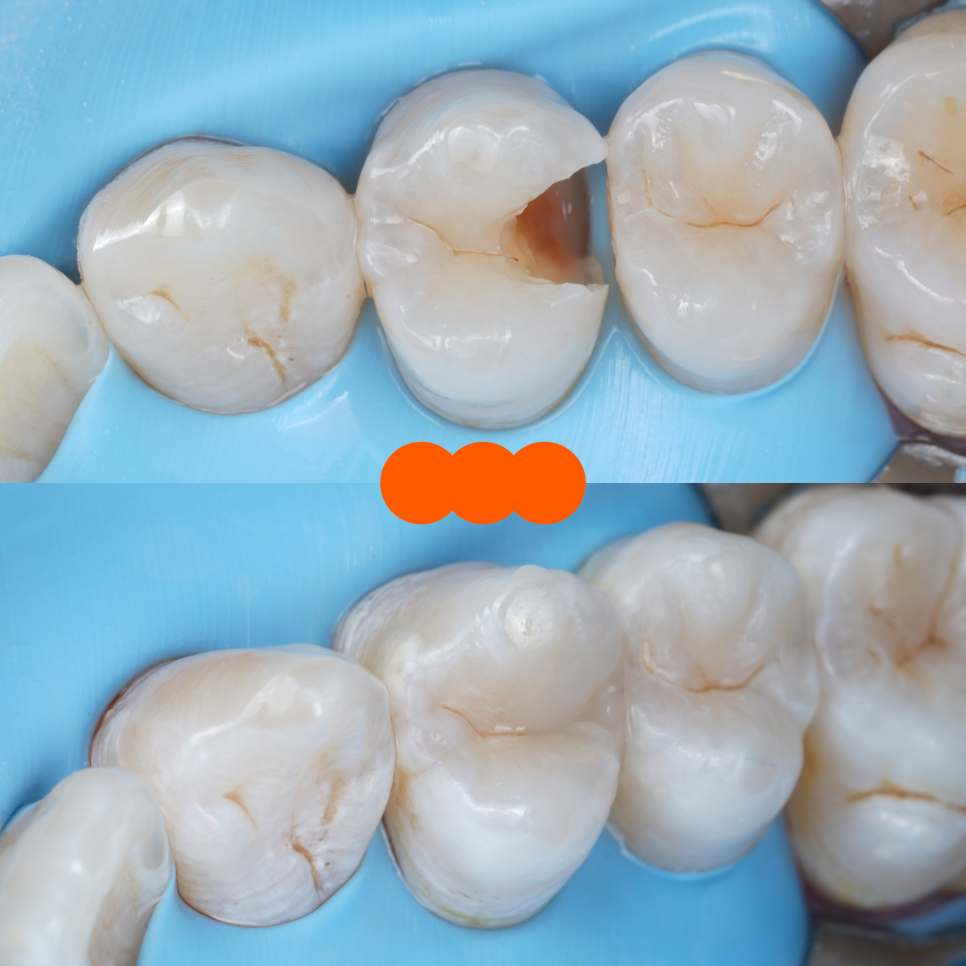

레진을 올려둔 곳을 못 알아보게끔

이번 치료는 단순히 떨어진 곳을 다시 붙인 게 아니라 치아를 지켜낸 치료였어요.

촬영일 : 251020

신경치료도, 크라운도 하지 않고 치아의 형태와 기능을 그대로 유지할 수 있었죠.

한 번 깎인 치아는 다시 재생되지 않기에 저는 항상 '어떻게 남아 있는 치아를 지키면서 복원할까?' 생각하며 진료하는데요.

그래서 이번 케이스처럼 신경치료 없이 최소삭제로 자연치 보존을 도와드리면 참으로 뿌듯하고 성취감을 느낍니다ㅎㅎ

이번 케이스처럼 크라운으로 씌우는 대신 자연치 그대로 복원하는 게 가능할 때는 언제나 그 길을 선택해요.